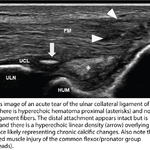

Ulnar collateral ligament sprain